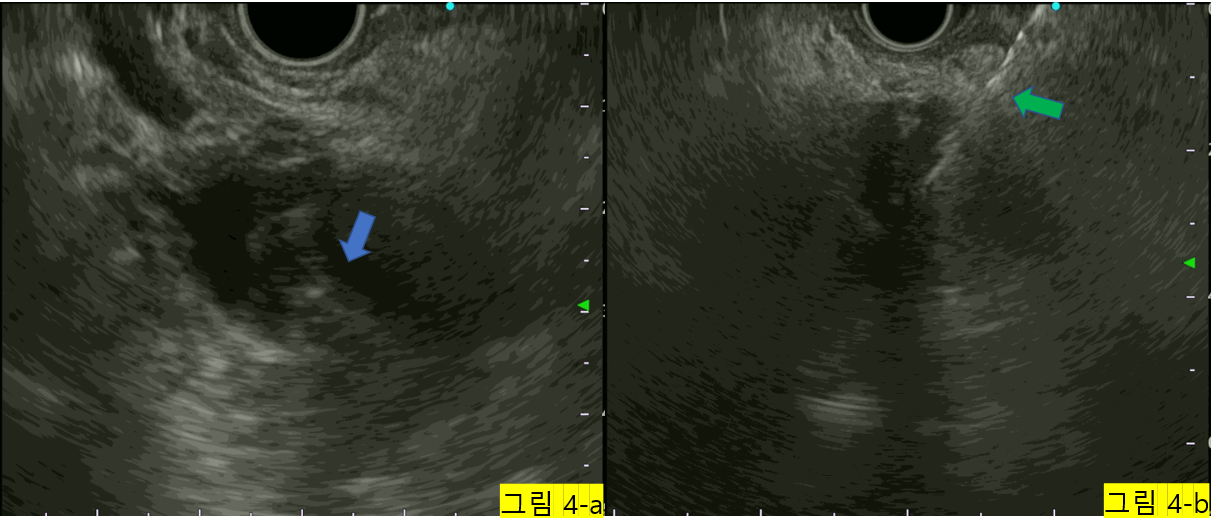

내시경 초음파를 사용하여 관찰하였을 때에 물혹 내부에 단단한 결절이 관찰되어 해당부위에서 조직검사를 시행하였습니다. (그림 4)

캡처_2025_01_01_14_33_04_665.png 그림 4-a. 물혹 내부에 단단한 결절이 의심된다. (파란 화살표) 그림 4-b. 내시경 초음파를 이용하여 바늘을 삽입하여 조직검사를 시행하고 있다. (녹색 화살표)

조직검사에서 비전형적인 세포(atypical cell)가 관찰되어 암이 숨어 있거나, 암 전 단계의 세포가 숨어 있을 가능성이 높다고 판단되어 췌장수술을 받기로 하였습니다.